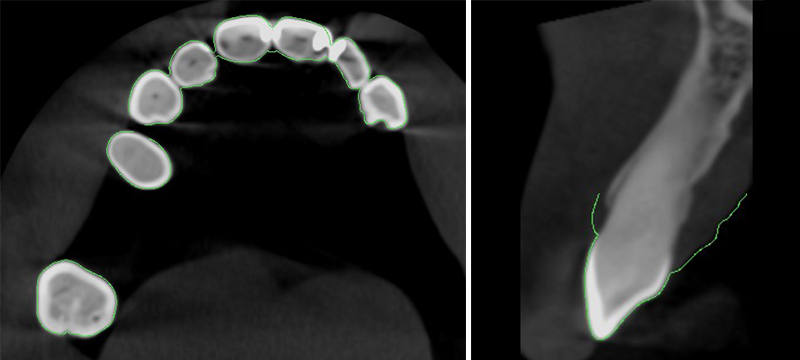

La fusion des images 3D et 2D est alors possible et réalisée. Pour vérifier le bon matching, nous vérifions si les contours du fichier STL se superposent correctement sur les contours des dents du dicom.

Fig. 05 : contrôle du matching.